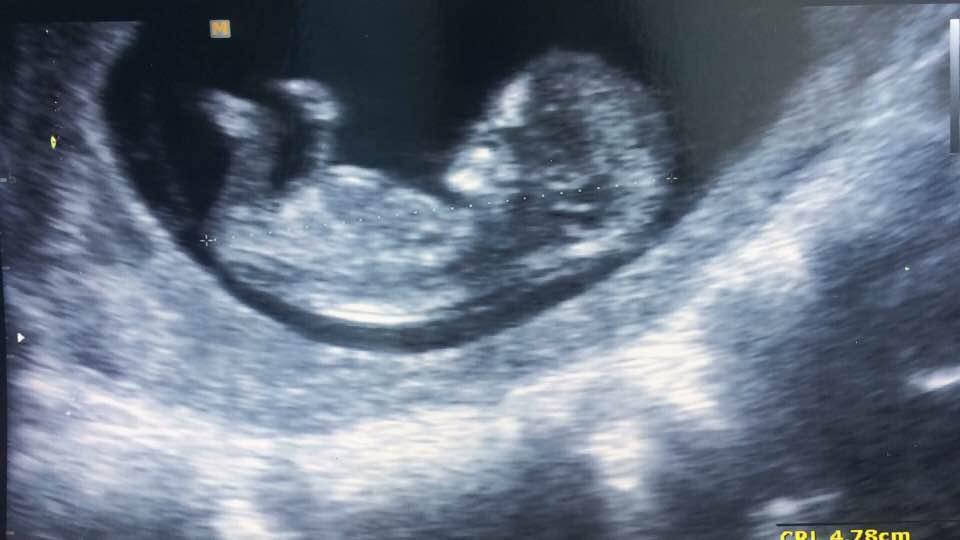

@malydiamant21 ne nedelala brala mi ster na streptokoka ani do me moc nestourala jen zrcadlem dneska sem spinila uz jen malinko tak snad to bude dobre na porod mame jeste cas chvilicku🙂jinak gratuluji krasna fotecka😍